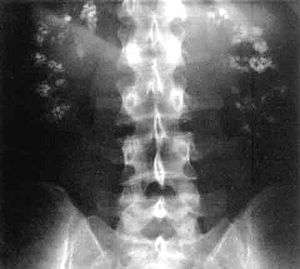

| Significant bilateral nephrocalcinosis (calcification of the kidneys) on a frontal X-ray (radiopacities (white) in the right upper and left upper quadrant of the image), as seen in distal renal tubular acidosis. | |

This leads to the clinical features of dRTA;[1] In other words, the intercalated cells' apical H+/K+ antiporter is non-functional, resulting in proton retention and potassium excretion. Since calcium phosphate stones demonstrate a proclivity for deposition at higher pHs (alkaline), the substance of the kidney develops stones bilaterally; this does not occur in the other RTA types.

- Nephrocalcinosis (deposition of calcium in the substance of the kidney)